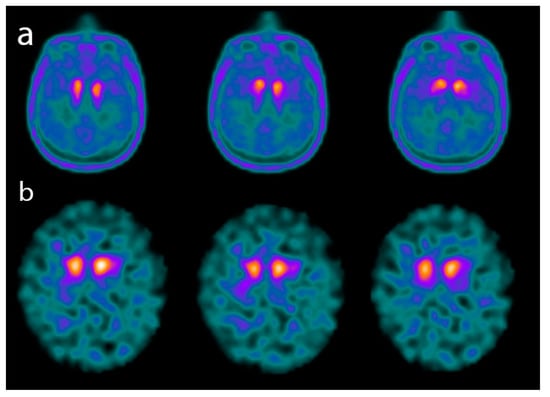

4.1. Dopamine Transporter (DAT) Imaging in SNCApathies

5.2. DAT Imaging in Other Atypical Parkinsonian Syndromes